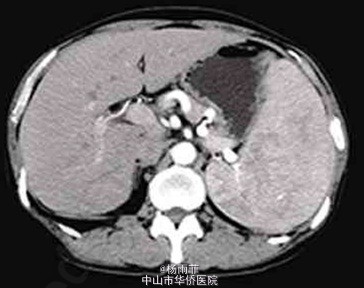

体格检查:体温37℃,脉搏84次/分,血压138/89mmHg,神志清楚,皮肤黏膜无苍白及黄染,浅表淋巴结未触及,颈软,双肺呼吸音清晰,心律齐,未闻及杂音,腹膨隆,触诊质软,无压痛,肝脾肋下未触及,移动性浊音阳性,双下肢不肿。 血常规检查:白细胞3.32×109/L,红细胞3.19×1012/L,血红蛋白93g/L,血小板273×109/L,尿常规及大便常规检查正常,肝肾功能正常,血清白蛋白正常,血淀粉酶534U/L(正常值125U/L),血清肿瘤标志物(甲胎蛋白、癌坯抗原、糖链抗原19-9)正常。 腹水常规检查:李凡他试验阴性,红色,细胞总数54473×106/L,白细胞473×106/L,单个核细胞95%,腹水生化检查:总蛋白35.9g/L,总胆固醇1.46mmol/L,乳酸脱氢酶122U/L,腺苷脱氨酶9U/L。腹水淀粉酶340U/L,腹水-血清白蛋白梯度14g/L。腹水细胞学检查见部分红细胞、淋巴细胞及间皮细胞,未见癌细胞。 乙型肝炎病毒表面抗原阴性,丙型肝炎病毒抗体阴性。 影像学检查: 胃镜检查示胃底静脉曲张,食管与胃黏膜未见异常; 门静脉CT成像显示脾静脉全程、肠系膜上静脉与脾静脉汇合处管腔明显变窄,以脾静脉为著,胃底静脉曲张,门静脉主干及肝内分支形态、走行未见明显异常,胰体头部钙化灶,尾部形态饱满,边缘模糊,见数个囊状影;腹腔大量积液。